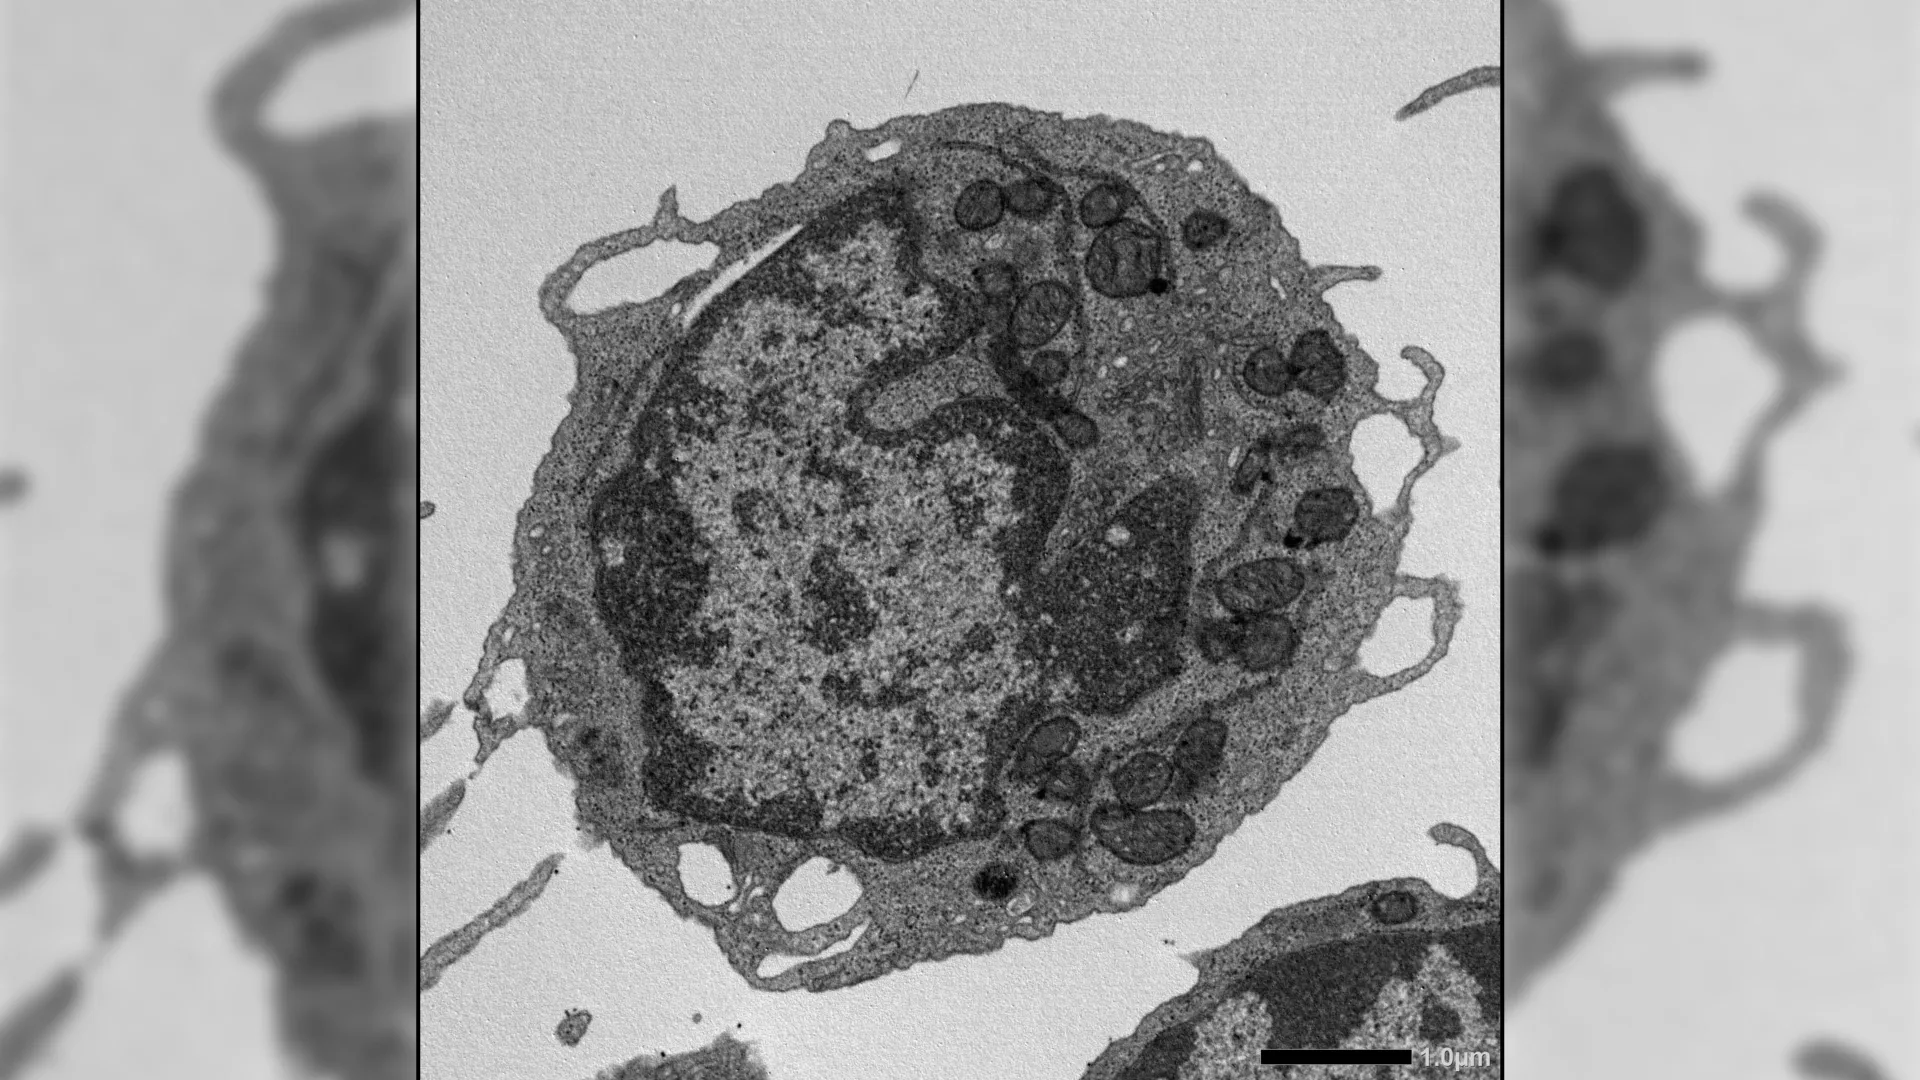

The results revealed a previously unknown role for MLKL in stem cell aging. Although MLKL is usually linked to cell death, its activation in HSCs did not increase cell death or reduce cell numbers. Instead, it acted in a different way.

When activated under stress, MLKL briefly moved to the mitochondria, the structures that generate energy within cells. There, it caused damage by lowering membrane potential, altering mitochondrial structure, and reducing energy production. These effects led to key features of aging in HSCs, including reduced ability to renew themselves, decreased production of lymphoid cells, and a shift toward myeloid cell output.